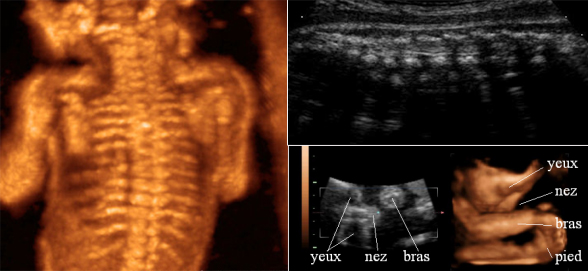

Le médecin s’intéresse particulièrement au squelette, au visage, au cœur et aux membres du fœtus. La modélisation en 3D offre l’avantage d’une visibilité accrue des os du fœtus. Ceux-ci forment une structure assez complexe, notamment avec la colonne vertébrale et les côtes, ce qui peut être difficile à distinguer, et à étudier en échographie 2D.

Figure 1 : Squelette du fœtus (échographie 3D)

Dans la Figure 1 : Les os sont très nettement visibles. Par conséquent, les images « en 3D » permettent d’évaluer plus facilement certaines malformations osseuses, par rapport aux images 2D (Figure 2) qui rendent le diagnostic plus long, plus difficile et moins précis.